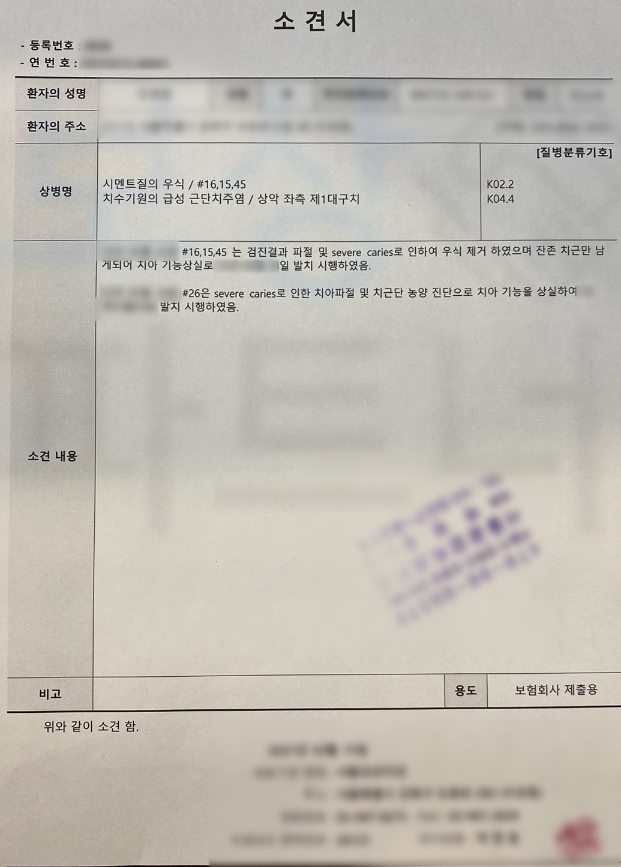

의뢰인은 비교적 젊은 나이였고 소견서 상 K02.2 와 K04.4 와 같은 치아 우식 등의 질환으로 청구했기에 당연히 지급되리라 생각하고 계셨습니다.. 하지만 돌아온 답변은 방금 살펴보셨던 것처럼 부지급 통보였죠.

의뢰인의 치아에 대해 K02.2 시멘트질의 우식증 K04.4 치수기원의 급성 근단 치주염 적용이라는 증거를 수집했고 약 2달간의 분쟁이 오간 결과 발치후 임플란트 보험금 인정 받을 수 있었습니다.